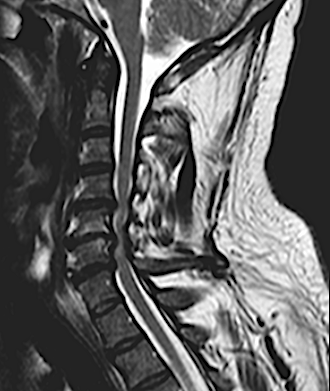

El paciente presentó a las 24horas un agravamiento de la paresia C7 derecha indolora, sin cambios en el puntaje (EMS) de su mielopatía, por lo que se decidió realizar una RM cervical urgente.

El resultado de la RM cervical planteaba dudas si era necesario o mandatorio realizar una descompresión posterior complementaria. Sin embargo, los parámetros clínicos no sugerían una compresión medular: la evolución lenta a la mejoría de su paresia, la ausencia de progresión de su mielopatía y la ausencia de dolor resultaron determinantes para que se adoptara una actitud conservadora. El paciente fue dado de alta (en plena pandemia de covid) y la evolución fue buena a pesar de que no pudo completar la rehabilitación. Se realizó nueva RM y RX cervical a los seis meses que resultó mucho más concluyente.

RM postoperatorio